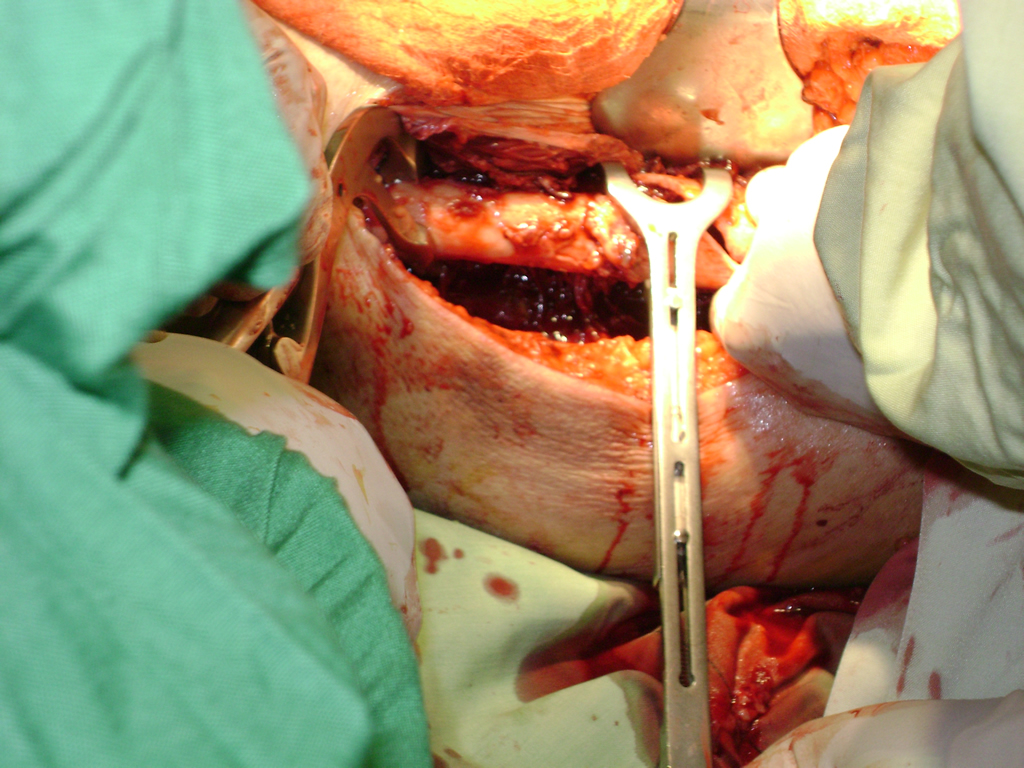

La cirugía de fractura de cadera se realiza para reparar una ruptura en la parte superior del hueso del muslo. Este hueso se denomina fémur.

Es parte de la articulación coxofemoral. Si una fractura de cadera no recibe tratamiento, es posible que deba permanecer en una silla o en la cama.

A menudo se recomienda la cirugía para reparar la fractura debido a dichos riesgos.